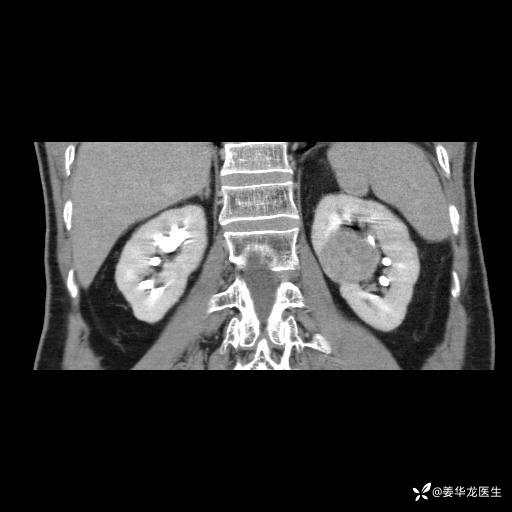

左肾中心型肾门部肿瘤39mm×34mm×36mm,右肾GFR25ml/min,部分切还是全切?

患者75岁老年男性,体重50kg,无高血压、肾病、糖尿病等基础病,检查发现左肾中心型肾门部肿瘤,右肾GFR只有25ml,无肉眼血尿,无镜下血尿。入院验血常规检查均正常,包括肾功能,肌酐102.7umol/L.

1.机器人辅助左肾部分切除术?

2.开放手术左肾部分切除术?

3.左肾根治疗切除术+透析